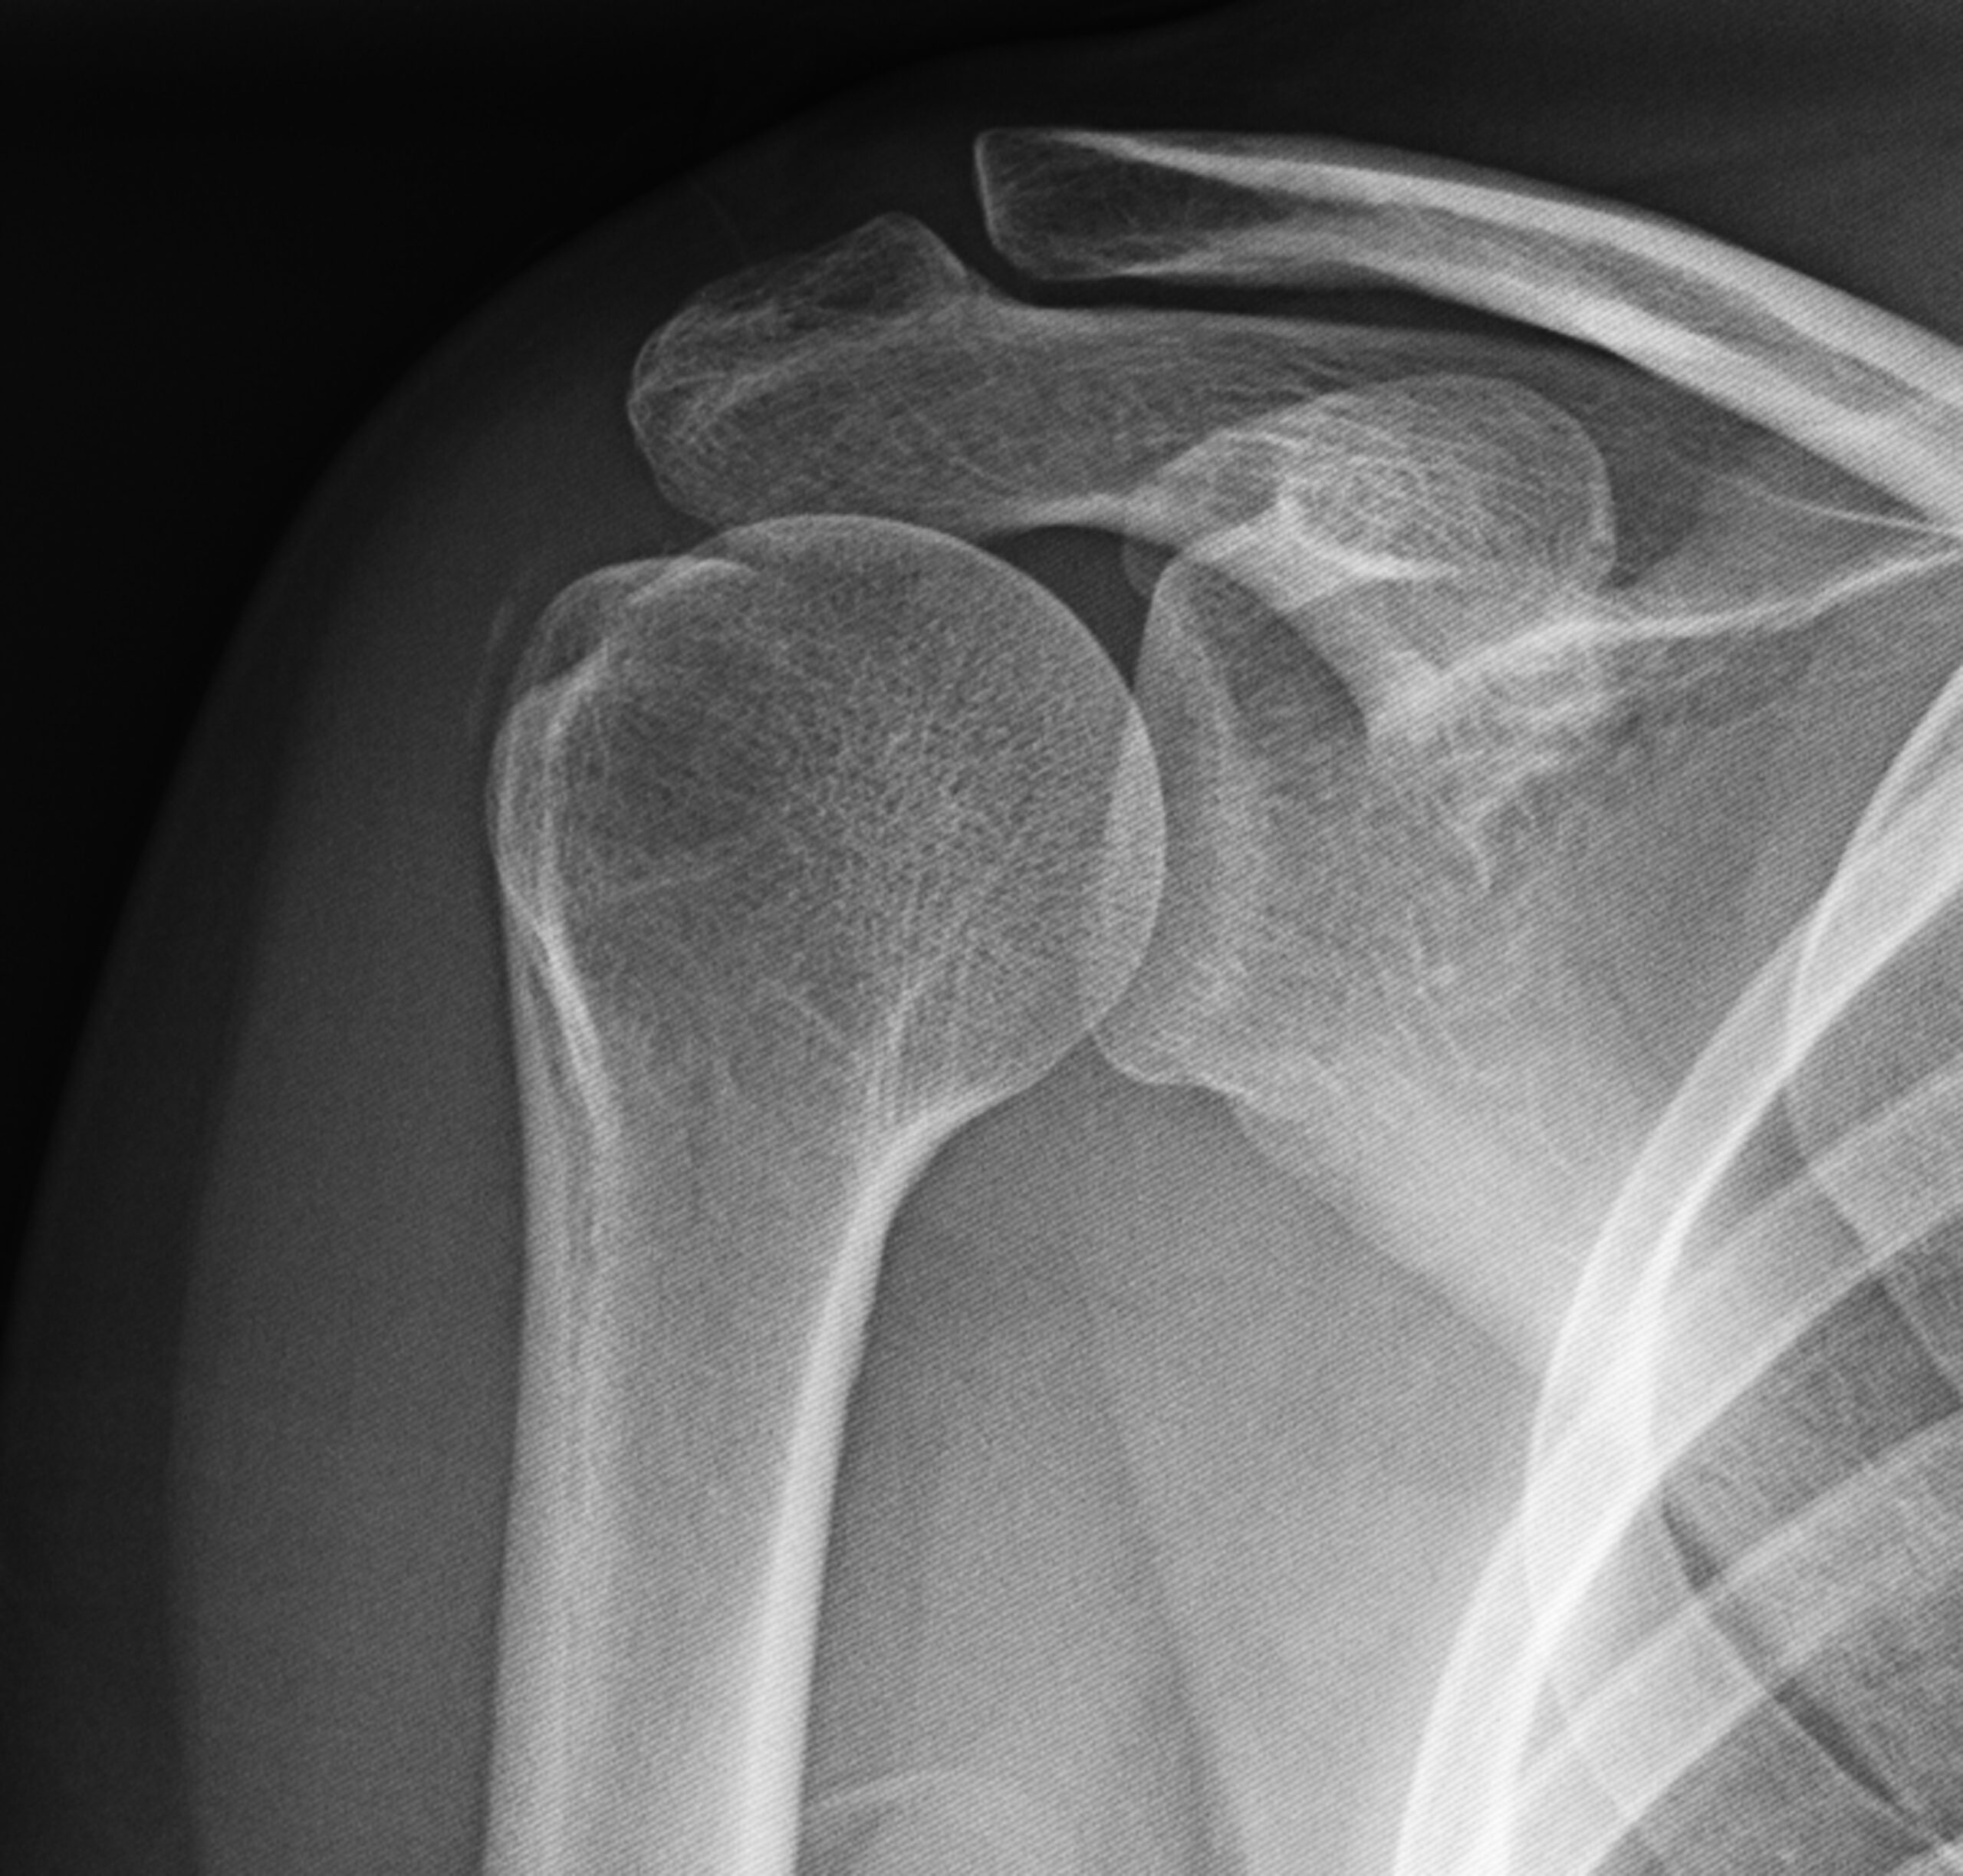

La radiografía nos permite evaluar la localización, la morfología, el tamaño y la densidad de las calcificaciones, pudiendo así clasificarlas. En el hombro, las proyecciones más útiles para tales efectos son la anteroposterior, outlet y las anteroposterior con rotación interna y externa.

La técnica del lavado ecoguiado de las calcificaciones de hombro consiste en la colocación de una aguja bajo anestesia local en el centro de la calcificación, de tal forma que mediante la inyección a presión de suero salino o anestésico se rompa la calcificación y se vacíe el material cálcico a la jeringa utilizada para el lavado. En la eco y Rx de control se visualiza reducción significativa de la calcificación: